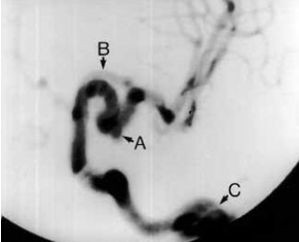

Aneurisma - cefalea a los 8 años en un PHACE

Las enfermedades neurovascular progresivas, se manifiestan como la formación de aneurismas,y/o estenosis, u oclusión arteriales,  son problemas preocupantes, pero su incidencia es desconocida. Los niños en situación de riesgo debe tener cuidado oftalmológico, neurológico y evaluación cardíaca